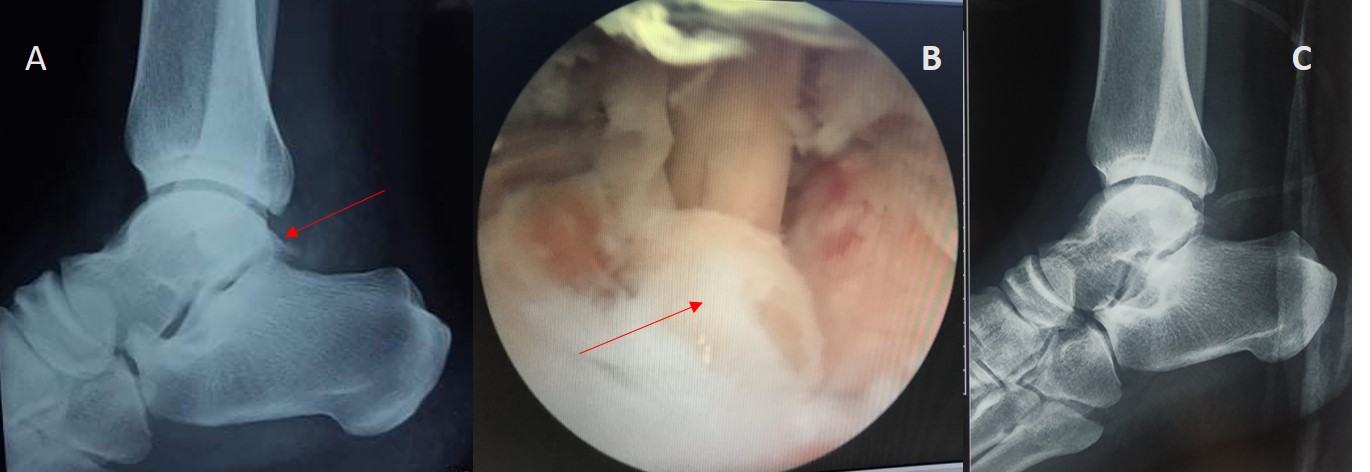

Hình 1: Bệnh nhân Nam 28 tuổi

A & B: Khối gai xương sau xương sên trên X quang trước mổ và hình ảnh nội soi trong mổ (mũi tên đỏ)

C: Hình ảnh tổn thương viêm gân gấp ngón cái dài trong mổ

Hình ảnh sau mổ trên X quang và vết mổ

Hình 2: Bệnh nhân Nam 45 tuổi

A: Hình ảnh khối gai xương trên X quang trước mổ (mũi tên đỏ)

B: Hình ảnh khối gai xương trong nội soi (mũi tên đỏ) và hình ảnh viêm gân gấp dài ngón cái và bao khớp sau

C: Hình ảnh X quang sau mổ